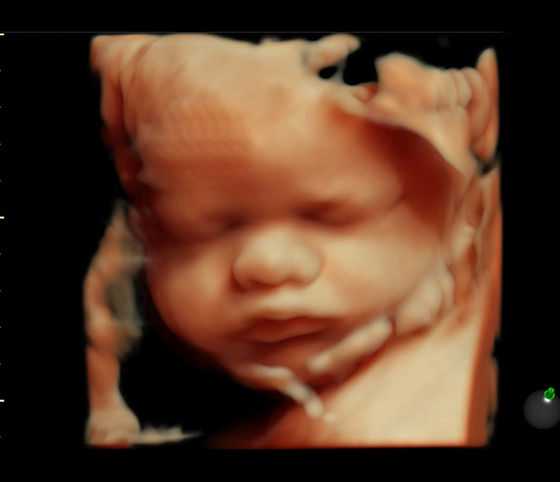

2、试管婴儿技术是治疗不孕不育的有效方法,操作环境要求高、技术难度大。